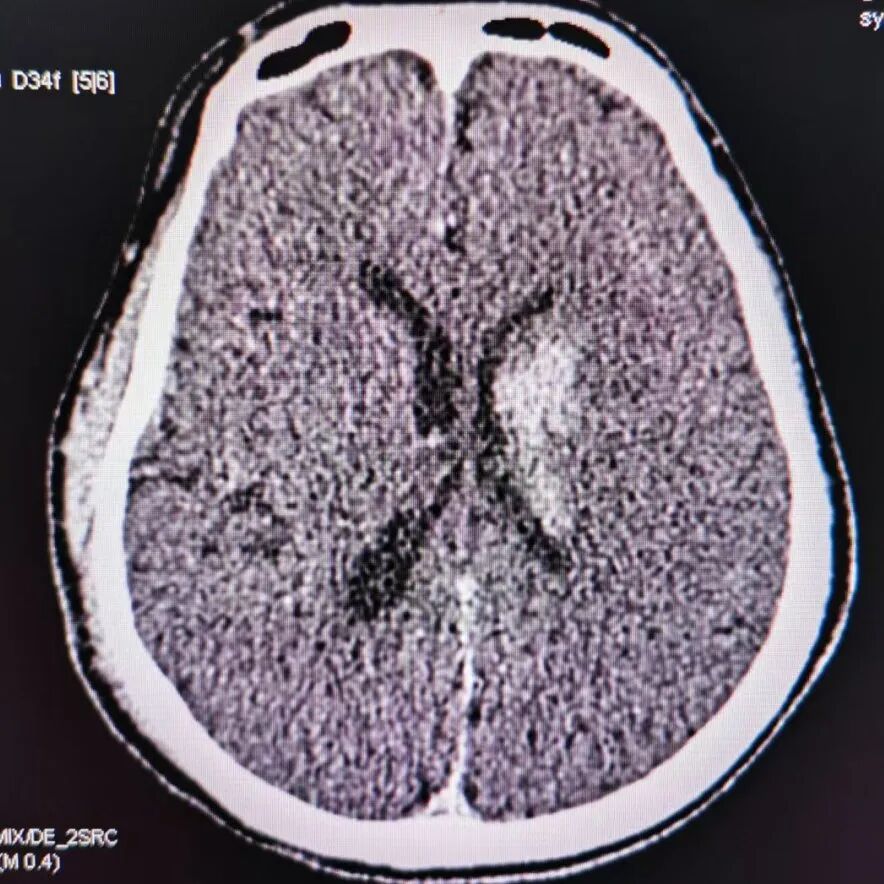

术后CT提示基底节区高密度灶。

动脉长鞘怎么置入有励可说|Locaste 088励楷长鞘及Tarvos微导丝在左侧大脑中动脉闭塞取栓术中的应用_https://www.jmylbn.com_新闻资讯_第22张

去碘后考虑造影剂外渗。